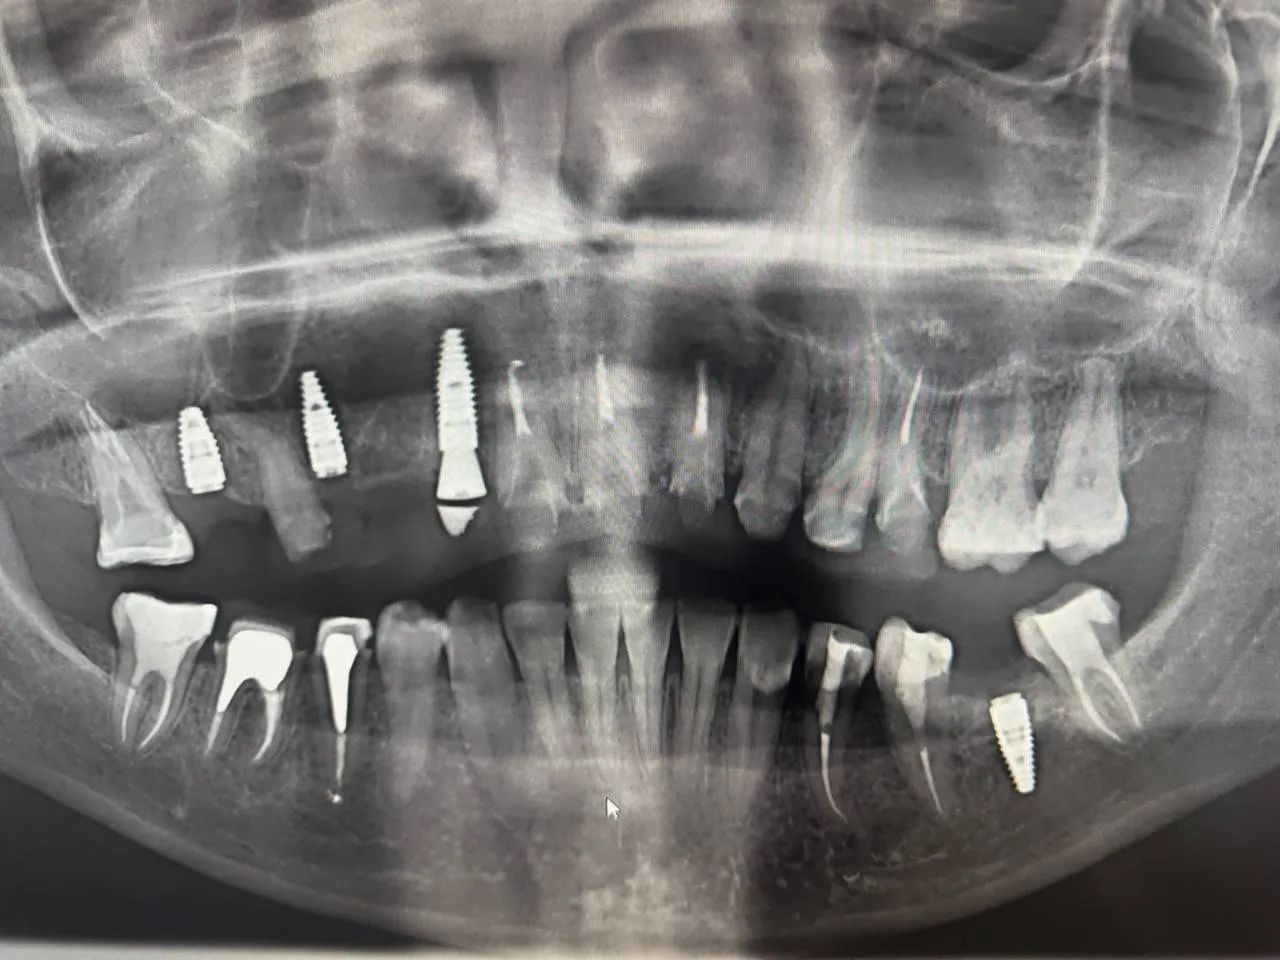

Single Implant with Bone Graft

Guided implant placement with simultaneous bone augmentation